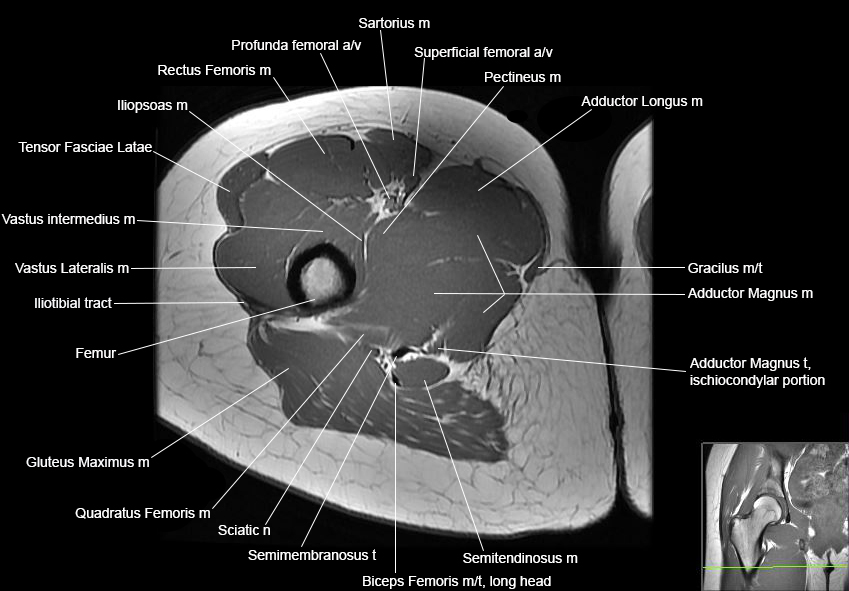

MRI Hip Anatomy

Scroll using the mouse wheel or the arrows